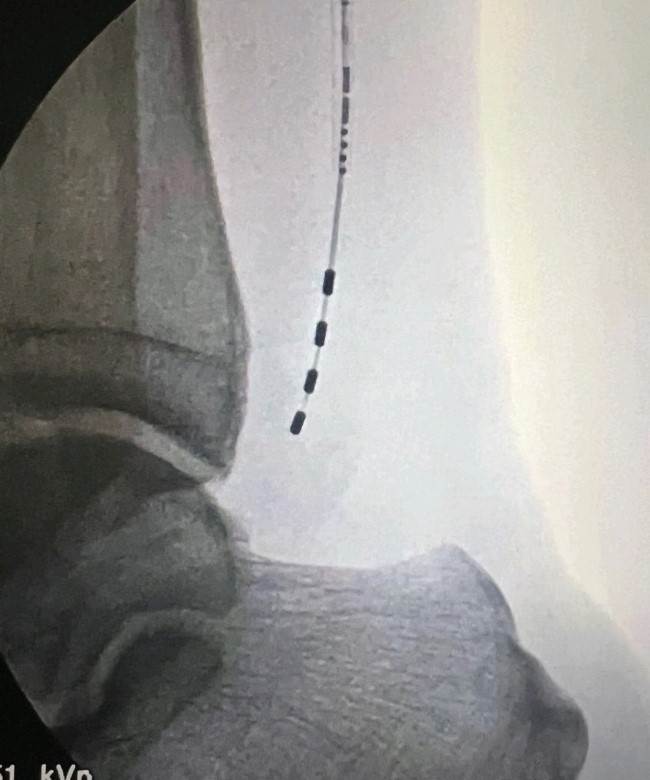

Η διέγερση των περιφερικών νεύρων αποτελεί μια προηγμένη τεχνική αντιμετώπισης του χρόνιου ανθεκτικού νευροπαθητικού πόνου περιορισμένης κατανομής. Αφορά σε εμφύτευση πολύ λεπτών ηλεκτροδίων κάτω από το δέρμα, κοντά στο πάσχον νεύρο, τα οποία μέσω ηλεκτρικής διέγερσης που χορηγείται από τη γεννήτρια της συσκευής, τροποποιούν την αντίληψη των μηνυμάτων πόνου από τον εγκέφαλο. Έτσι ο ασθενής αντιλαμβάνεται το επώδυνο ερέθισμα σαν μυρμήγκιασμα ή ήπιο καύσος. Η γεννήτρια της συσκευής εμφυτεύεται υποδορίως σε κοντινή περιοχή και οι παράμετροι της διέγερσης ρυθμίζονται μέσω εξωτερικού προγραμματιστή. Πλέον υπάρχουν και συστήματα νευροδιέγερσης, τα οποία δεν απαιτούν εμφύτευση γεννήτριας υποδορίως, και λειτουργούν μέσω ενός πομπού που επικολλάται σαν patch στο δέρμα.